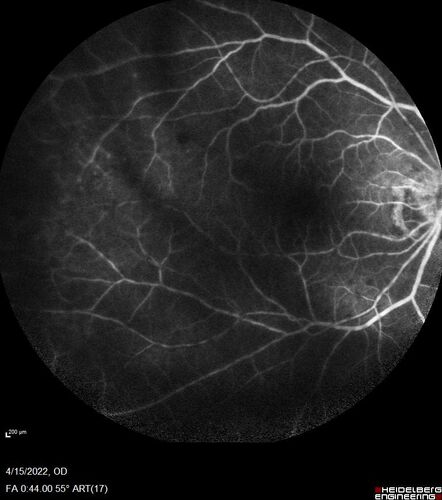

Toxoplasmosis right eye with diffuse retinal vascular whitening PCR confirmed

66 year old man The patient was doing fine until about 2-3 months ago.  He woke up with shadows and spots in the right eye.  Every blue moon he gets some pain in the right eye.  He has been getting treated with eye drops in the right eye.  Since this happened the vision is mostly the same.  Sometimes he sees better than other times.  He has not been treated with oral medications.

VA OD: sc20/63-1 OS: sc20/20

IOP: TP: OD:15 OS:20

Negative labs: ACE, Lysozyme, RPR, HLA B27, Quant TB Gold, ESR (slight elevation of CRP)

PCR anterior chamber: negative herpes virus (HSV, VZV, CMV)

Positive for toxoplasmosis